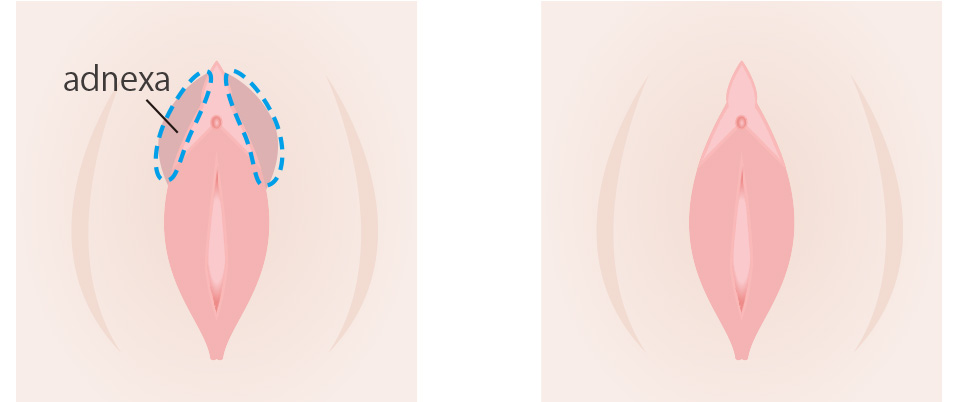

This surgery removes the folds in the front of the labia minora that continue with the clitoral foreskin. The shape of the adnexa depends on the individual; some have two folds, while others have only one. Dirt and grime can easily accumulate between the folds, which can cause odor and irritation. It is effective to perform the surgery at the same time as labia minora reduction for overall balance.

Recommended for people with these problems